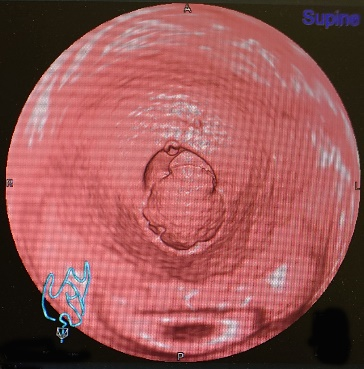

1)CTコロノグラフィーとは

CTコロノグラフィーとは、肛門・直腸から全大腸へ空気を注入したうえでCT撮影を行い、画像処理を行って実際の内視鏡でのぞいているように画像を再構成する方法です。実際の検査では、内視鏡より少ない量の下剤を服用し大腸の中を空にして、当日、CT検査台の上でお尻から炭酸ガスを注入し、CT撮影を行います。炭酸ガスを入れるため、おなかが張った感じがしますが、痛みはほとんどありません。撮影は仰向けとうつ伏せの2回行いますが、10分前後で終了します。

CTコロノグラフィの画像